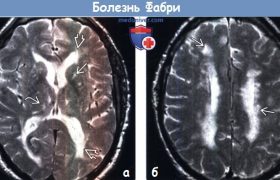

Болезнь Фабри

Болезнь Фабри — редкое жизнеугрожающее заболевание, поражающее различные органы и системы. Признаки и симптомы у пациентов могут различаться, но в большинстве случаев болезнь имеет неврологические, нефрологические и кардиальные проявления.

Болезнь Фабри является наследственным, сцепленным с Х-хромосомой, прогрессирующим, полиорганным, редким заболеванием, которое может поражать как мужчин, так и женщин любого возраста и этнической принадлежности. Оно впервые...